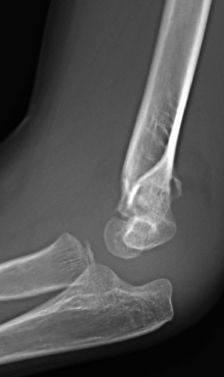

Figura 8: a-d, Imagen radiografica de fractura del cóndilo lateral con desplazamiento articular. Tratamiento quirúrgico mediante reducción abierta y osteosíntesis.